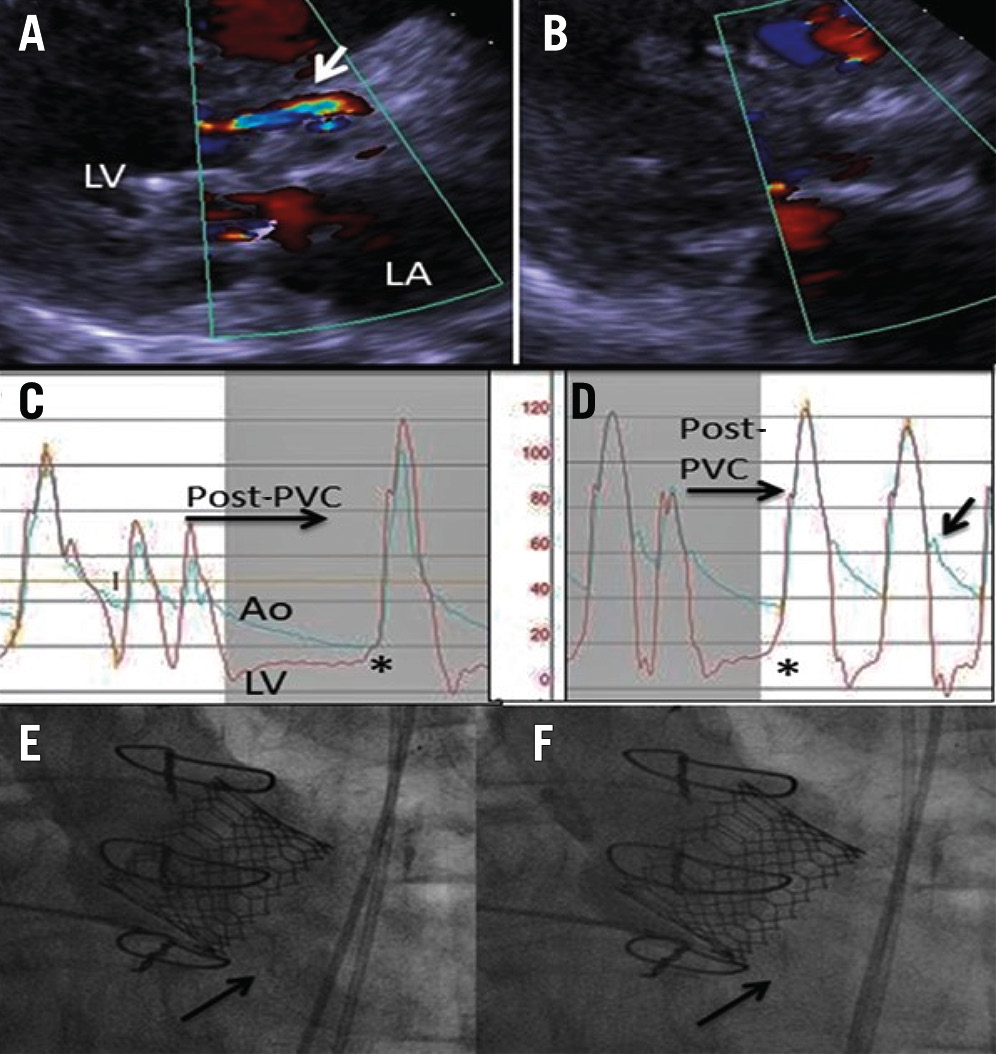

In contemporary practice, aortic regurgitation (AR) is assessed using the following three specific modalities: echocardiography, haemodynamics, and aortography. Although transthoracic and transoesophageal echoÂcarÂdioÂgraphy (TOE) have long been a mainstay for diagnosis of the type and degree of AR, they may sometimes be limited in accuracy and reproducibility5354. However, echocardiography is an important tool for AR assessment, in addition to other potential complications, and is almost indispensable for distinguishing paravalvular versus valvular AR. At our institution, we also place substantial emphasis on haemodynamic assessment in our TAVI procedures, carefully comparing both aortic diastolic and LV end-diastolic pressures (LVEDP) before and after TAVI, the quality of the dicrotic notch after TAVI, slope of the LV diastolic pressure increase, and response of the LVEDP and aortic diastolic pressure to the long RR interval following a premature ventricular contraction (Figure 5). Several prognostically relevant haemodynamic indices have been proposed, with the AR index (calculated as LVEDP–DBP/SBP, in which DBP is the diastolic blood pressure and SBP is the systolic blood pressure) being the most widely adopted5556. Aortography is also an important part of our post-TAVI implantation routine. It allows assessment of coronary flow, confirmation of depth of implantation, insight into annular trauma, and, most importantly, an adjunctive assessment of AR.

Figure 5. Paravalvular regurgitation before and after post-dilatation. The transthoracic echocardiography demonstrates anterior PVR (arrow) before (A) and after (B) post-dilatation. The haemodynamic evaluation demonstrates the lack of an aortic dicrotic notch, aortic diastolic/LVEDP equalisation with a long RR interval after a PVC (asterisk) before post-dilatation (C), and a prominent dicrotic notch (arrow) and good aortic diastolic/LVEDP separation (asterisk) after post-dilatation (D). The aortogram demonstrates LVOT opacification during diastole (arrow) after TAVI (E) which is corrected by post-dilatation (F). Ao: aorta; LA: left atrium; LV: left ventricle; LVEDP: left ventricular end-diastolic pressure; LVOT: left ventricular outflow tract; PVC: premature ventricular contraction; PVR: paravalvular regurgitation; TAVI: transcatheter aortic valve implantation